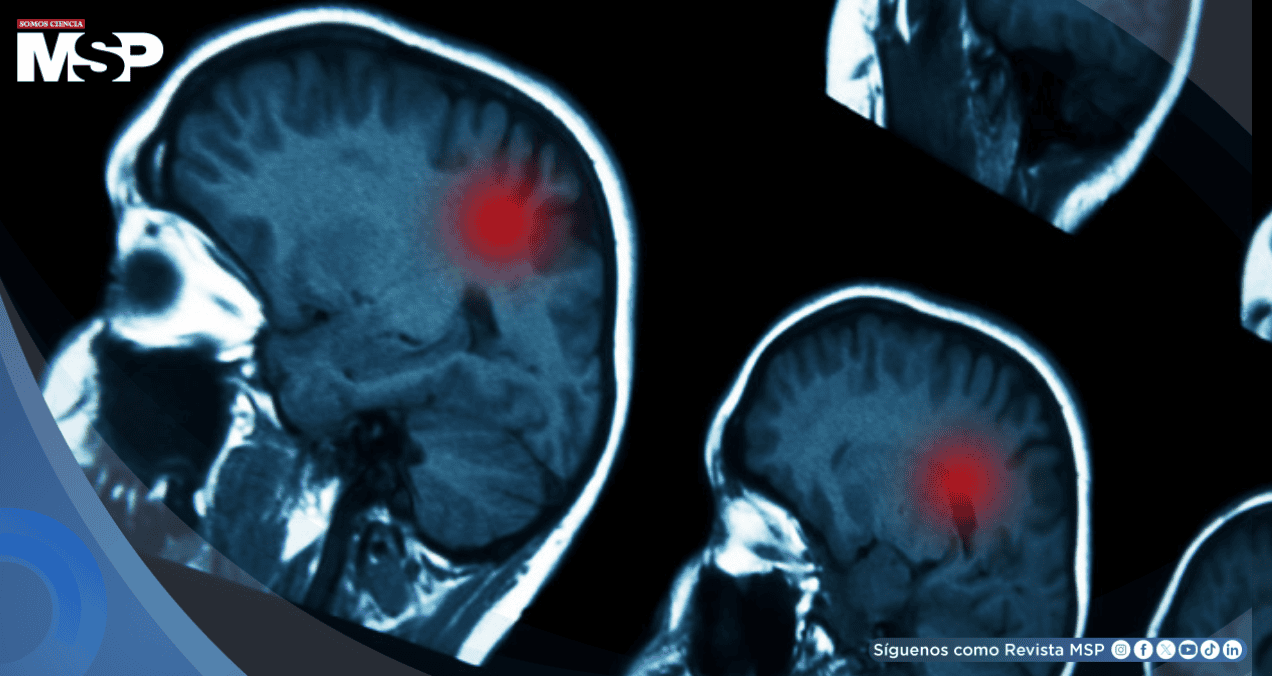

Estudio revela una asociación entre lesiones cerebrales severas y el desarrollo de cáncer cerebral años después, aunque el riesgo general sigue siendo bajo

Una investigación científica estadounidense ha establecido por primera vez una conexión directa entre los traumatismos craneoencefálicos moderados y graves con un mayor riesgo de desarrollar tumores cerebrales malignos varios años después de la lesión inicial.

Los resultados mostraron que el 0,6 por ciento de los participantes que habían sufrido traumatismos moderados y graves desarrollaron tumores cerebrales entre 3 y 5 años después del evento inicial.

Resulta especialmente relevante que en los casos de traumatismos leves no se observó esta asociación, lo que sugiere una relación directa entre la gravedad de la lesión y el riesgo posterior.